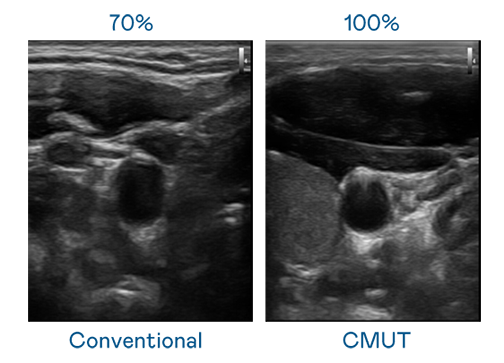

CMUT 技术是一种用电容式微机电元件来产生超音波讯号的技术。与传统 PZT 压电式技术相比,CMUT 频宽增加 30%,更宽频的超音波讯号让影像解析度大幅提升,是实现高影像品质医疗超音波扫描、促进精准医疗发展的关键技术。

大频宽带来超清晰影像

超音波影像的解析度高低,首先取决于探头能发出的讯号频宽。彩神 CMUT 可提供高清晰的超音波讯号,提供高频宽、高灵敏度、影像纹理细节更高的超音波影像,协助医护人员缩短影像判读时间及利用精准的医疗影像进行诊断。